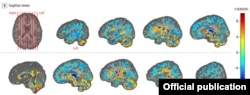

Las imágenes revelaron “diferencias significativas en el volumen de materia blanca cerebral total, [en] volúmenes locales de materia blanca y gris”, y en la integridad microestructural del tejido del cerebelo. También mostraron diferencias de “conectividad en las subredes auditivas y visoespaciales, pero no en la subred de control ejecutivo”.

En declaraciones al periódico británico The Guardian, Verma observa que los resultados de la investigación son desconcertantes, porque los cerebros de los diplomáticos mostraron lo contrario de lo que comúnmente aparece cuando hay daño cerebral.

En vez de dilatarse, la región llamada vermis –que ayuda a coordinar los movimientos del tronco y de las extremidades y maneja señales visuales y auditivas-- se contrajo, y lejos de disminuir, un factor de análisis clínico llamado anisotropía fraccional aumentó.